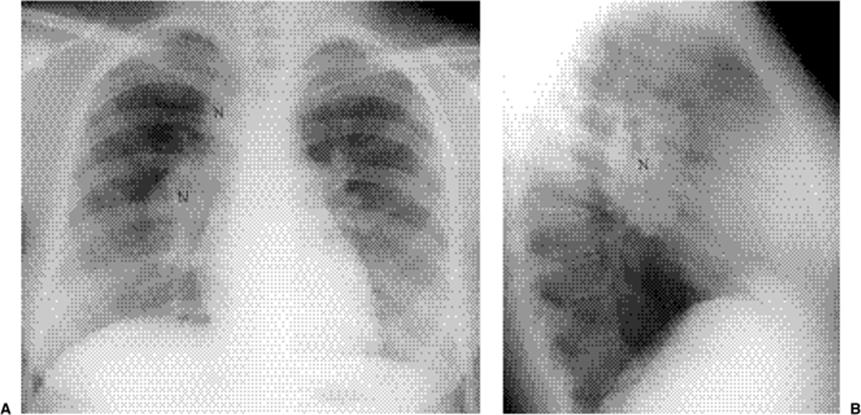

The CXR in primary TB commonly reveals lymph node enlargement (Fig. 5.24), especially involving the right paratracheal and hilar lymph nodes. The prevalence of lymph node enlargement decreases with age, from 40% of young adults to 10% of the elderly. Homogeneous consolidation in a segmental or lobar distribution is the most common parenchymal abnormality (Fig. 5.25). Patchy, linear, or nodular disease occurs less commonly. There is said to be a slight right lung predominance, but no zonal predominance. In contrast to lymph nodes, parenchymal disease increases in frequency with age. The initial site of parenchymal involvement at the time of first infection is known as the Ghon focus. The Ghon focus and enlarged regional lymph node together are known as the Ranke complex. Simon foci are apical nodules, frequently calcified, that result from hematogenous seeding at the time of initial infection. Prevalence of pleural effusion increases with age. Effusion is seen in one-third of adults, often on the side of parenchymal abnormality. Effusions are usually unilateral, with bilaterality in 15% of cases. In 5% effusion is the sole abnormality.

Figure 5.24 Primary tuberculosis. (A) Posteroanterior and (B) lateral chest radiographs demonstrate right hilar and paratracheal lymph node enlargement (N).

Contrast-enhanced CT may show a characteristic appearance in mediastinal tuberculous lymphadenitis, with central nodal low attenuation (Fig. 5.26) and peripheral enhancement. This appearance also occurs with atypical mycobacterial infections, lymphoma, metastases, and Whipple disease. CT is more sensitive for detection of calcification.

Figure 5.26 Primary tuberculosis. Computed tomography demonstrates low attenuation of a subcarinal lymph node (arrow).